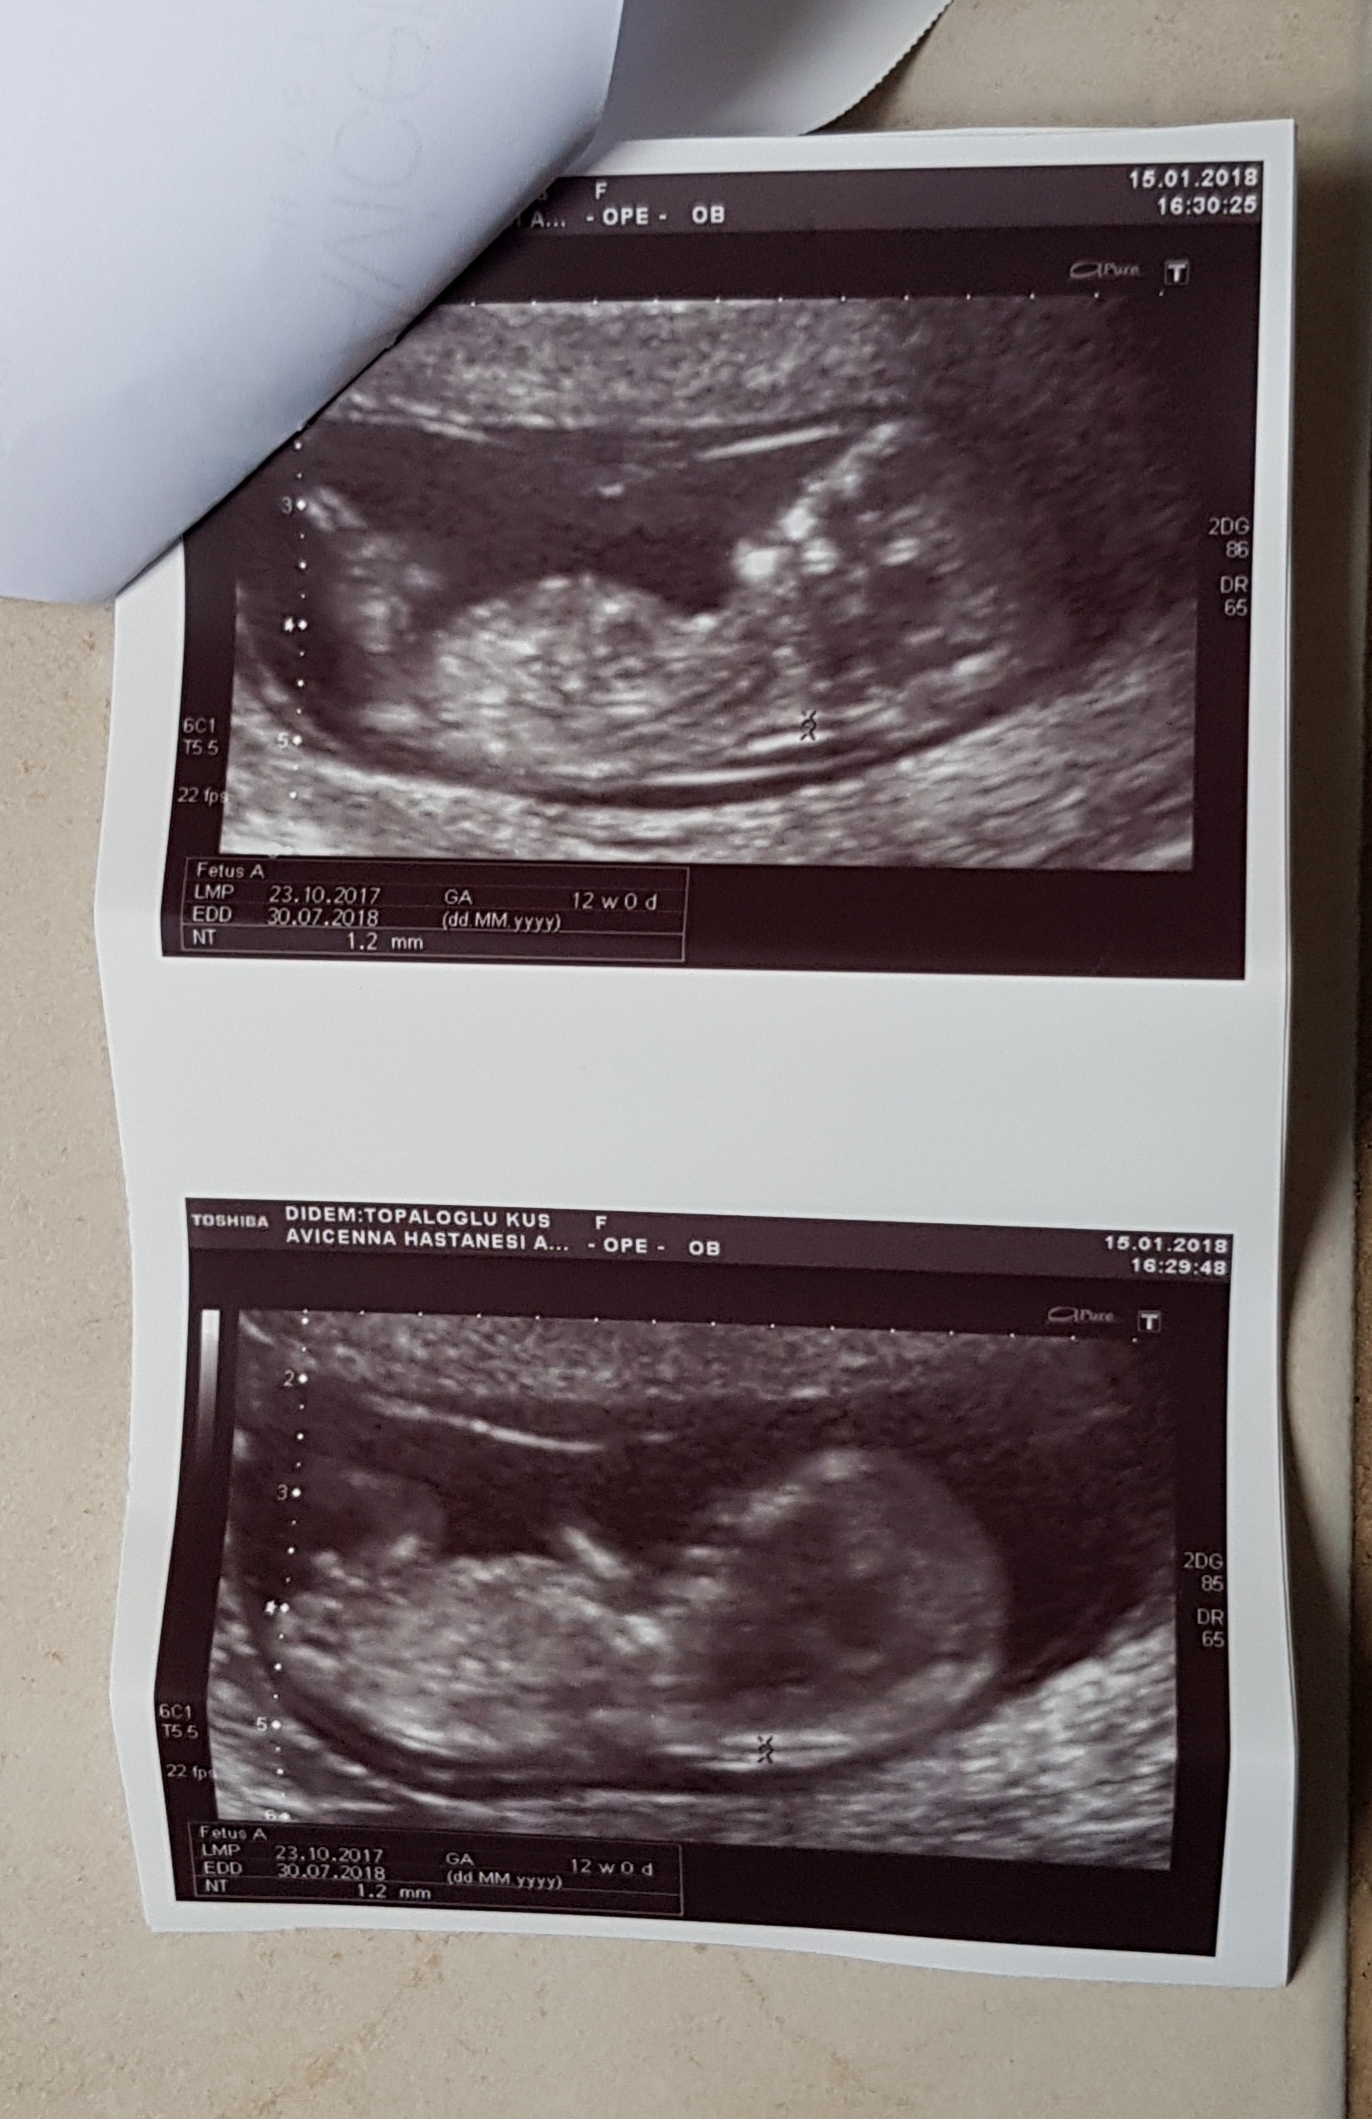

Anlaşılan o ki bebek süpriz yapmak istiyor. Evet burda da belli değil. Hayırlısı olsun. 16-17 -20 . haftalar da net olarak bebeğinizin cinsiyetini öğrenebilirsiniz. 12-13 . haftalarda cinsiyet tahminin de yanılmalar olabiliyor. Sağlıklı gebelik geçirmeniz dileği ile.

13 haftalikken erkek dedi doktor 13+6 kiz gibi dedi benimde kafam karisti🙂 bir hafta sonra tekrar gidicem 16+4 olacak o zaman netlesir insaAllah.tekrar tesekkur ederim ♡

Doktorlar ultrasonla anlık olarak cinsiyeti görebilir. Size verilen görseller de anlardan bir kesit. Doktorun gördüğü anla size verilen usg görüntüsü farklı olabilir. Belirttiğim gibi 12-13 haftalarda cinsiyet tahminleri yanıltıcı olabilir. Bir kaç koşul yanılmaya neden olabilir. Bir daha ki kontrolde bebeğin pozisyonu uygunsa cinsiyetini öğrenebilirsiniz. Rica ederim, sevgiler.

Merhaba, emin olmamakla birlikte bebeğinizin cinsiyetinin erkek olduğu kanaatindeyim. Bebeğinizin cinsiyetini net olarak 16-17-20. haftalarda öğrenebilirsiniz.